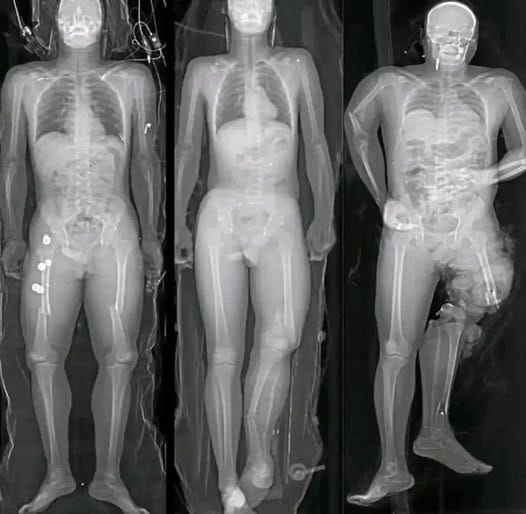

Medical research has identified a small number of myocarditis cases—an inflammation of the heart muscle—following certain mRNA vaccines, particularly among adolescent and young adult males. However, context is critical. These cases are rare, typically mild, and most individuals recover fully with minimal treatment.

Multiple peer-reviewed studies show that the risk of myocarditis from COVID infection itself is significantly higher than the risk associated with vaccination. COVID-19 as a disease has been linked to more severe cardiac complications, including inflammation, blood clots, and long-term heart damage.